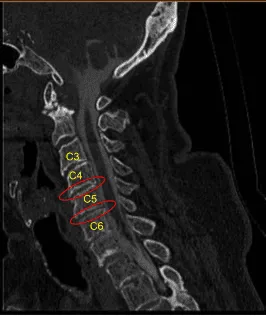

Este paciente acudió a la consulta ambulatoria con signos y síntomas de radiculopatía espondilótica cervical. Tras un fracaso extenso con tratamientos no quirúrgicos y un síndrome de dolor progresivamente severo, se recomendó la cirugía para descomprimir y estabilizar la columna cervical.

Estaban colocados en posición supina sobre la mesa de quirófanos, con la cabeza en una ligera extensión y los hombros suavemente pegados con cinta para visualización fluoroscópica. Se utilizó fluoroscopia para localizar el nivel del índice C5. La piel se limpió con clorhexidina. Se demarcó una incisión transversal en el lado derecho.

Se utilizó el monopolo Bovie para exponer la columna cervical anterior de C4 a C6, socavando los músculos del largo del cóleo bilateral. Se instaló un sistema de separador autoretenedor TrimLine. Se colocaron clavos de cáscaro de 12 mm en los cuerpos vertebrales anteriores C4, C5 y C6. Se aplicó primero una retracción suave en C5-6.